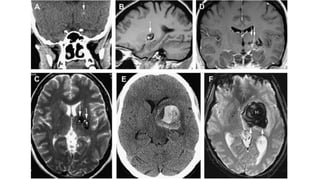

Causas y patrones en neuromagén: MALFORMACIONES VASCULARES CEREBRALES

CAVERNOSAS

• La pared delgada sin musculo ni tejdo

elástico.

• Microhemorragias crónicas.

• Riesgo de re sangrado 4.5- 26% por año.

• La hemorragia es más pequeña que con las

AV.

• Puede contener calcificaciones.

• Imagen de crispeta.

• Venas tubulares que drenan a al seno o a la

superficie ependimaria